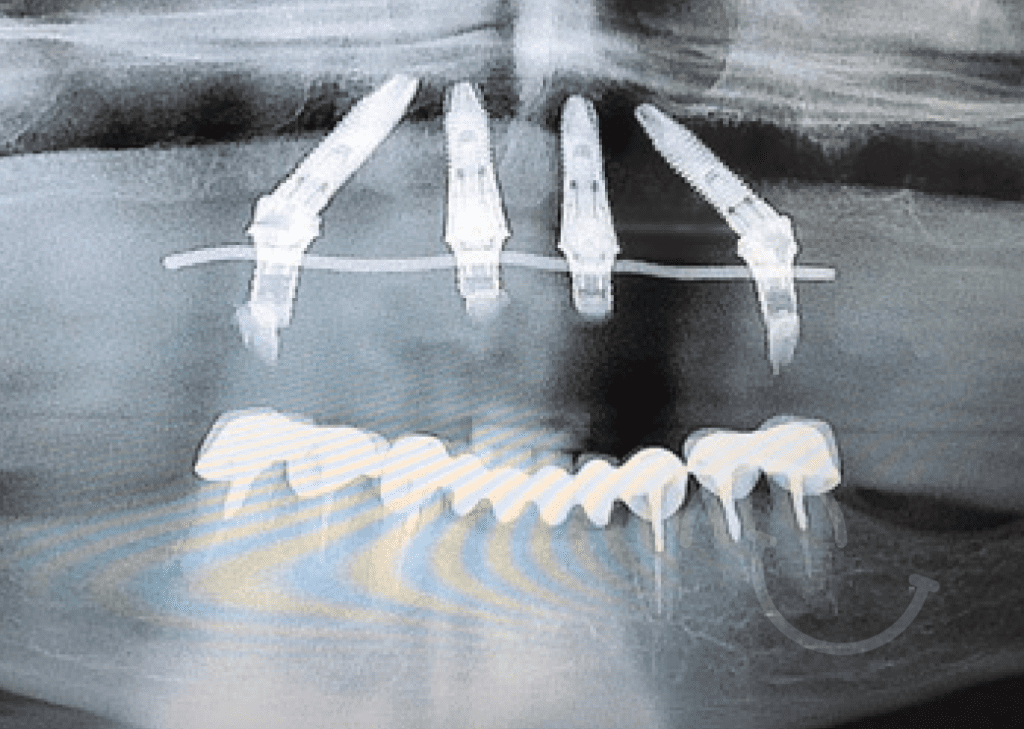

Casos clínicos de implantes dentales